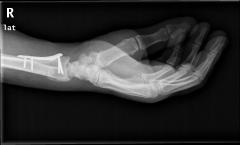

Υπάρχουν διάφορες χειρουργικές τεχνικές και υλικά που χρησιμοποιούνται, ανάλογα με τη μορφολογία του κατάγματος. Μετεγχειρητικώς ενδέχεται να εφαρμοστεί ολιγοήμερη ακινητοποίηση. Εαν απαιτηθεί φυσιοθεραπεία, αυτή είναι καλό να γίνεται μετά την 6η μετεγχειρητική εβδομάδα.

Περίπτωση 2ου ασθενούς